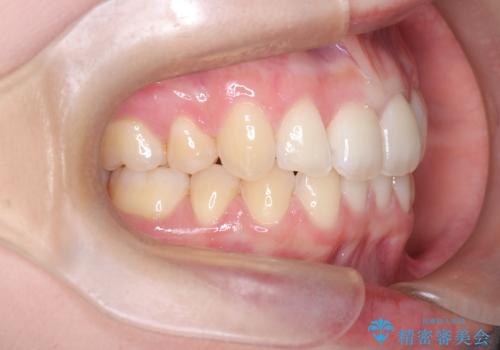

抜歯矯正×インビザライン|上下のバランスを整え、美しい歯並びへ

- 患者様は、上下の噛み合わせのバランスが悪く、特に上顎の前歯の突出を気にされて来院されました。診査の結果、下顎の歯並びに合わせて上顎を後方へ移動させる必要があると判断し、上顎の小臼歯2本を抜歯することを提案しました。目立たない矯正を希望されたため、**インビザライン(マウスピース矯正)**を選択。計画的にスペースを作りながら、バランスの取れた歯並びを目指しました。

治療はまず、上顎の小臼歯を2本抜歯し、そのスペースを利用して前歯を後方へ移動させました。インビザラインはアタッチメントを併用し、より効率的に歯を動かせるよう調整。定期的なチェックとアライナーの交換を続け、約3年かけて理想的な歯並びと噛み合わせを実現しました。治療後はリテーナーを使用し、安定した状態を維持。患者様からは「口元がスッキリし、横顔の印象も変わった」と嬉しいお声をいただきました。